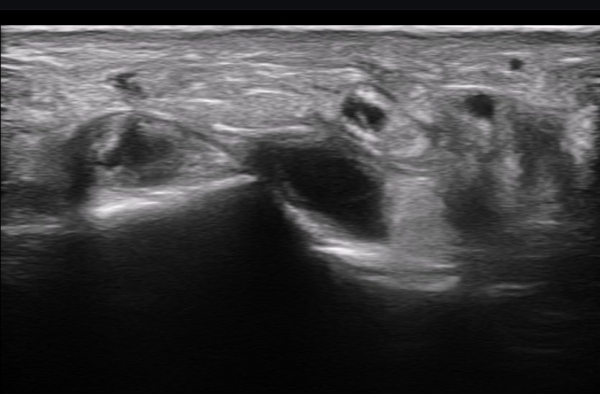

ÃÊÀ½ÆÄ ¼Ò°ß : ºñº¹½Å°æ Ⱦ´Ü¸é°Ë»ç¿¡¼­(»çÁø 1~13) ºñº¹½Å°æÀÇ Àú¿¡ÄÚ ºÎÁ¾°ú ´Üºñ°ñ°Ç³» ³¶Á¾¼º º´º¯ÀÌ °üÂûµÈ´Ù.

ºñº¹½Å°æ Á¾´Ü¸é°Ë»ç(»çÁø 14, 15)¿¡¼­ ºñº¹½Å°æÀÇ Àü¹ÝÀûÀÎ Àú¿¡ÄÚ ºÎÁ¾°ú ºñº¹½Å°æ ½ÉÃþÀ¸·Î ´Üºñ°ñ°Ç³»

³¶Á¾¼º º¯º¯ÀÌ °üÂûµÈ´Ù.